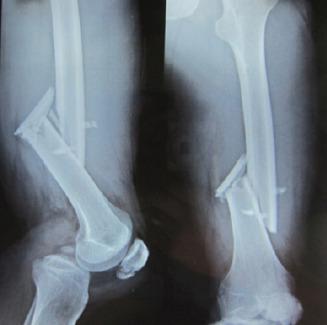

A 23-year-old male who sustained a high-energy trauma due to road traffic accident. He presented to ER with fracture of shaft femur, multi-ligament injury at the ipsilateral knee, fracture lower pole patella, ipsilateral fracture talus, and calcaneus along with comminuted fracture femoral head. He was managed by open reduction and internal fixation of the femoral head by safe surgical dislocation of the hip joint. Such injuries have been described rarely in the literature until now. The purpose of this report is to highlight the extreme rarity, possible mechanism involved, surgical management, and functional outcomes of such injuries.